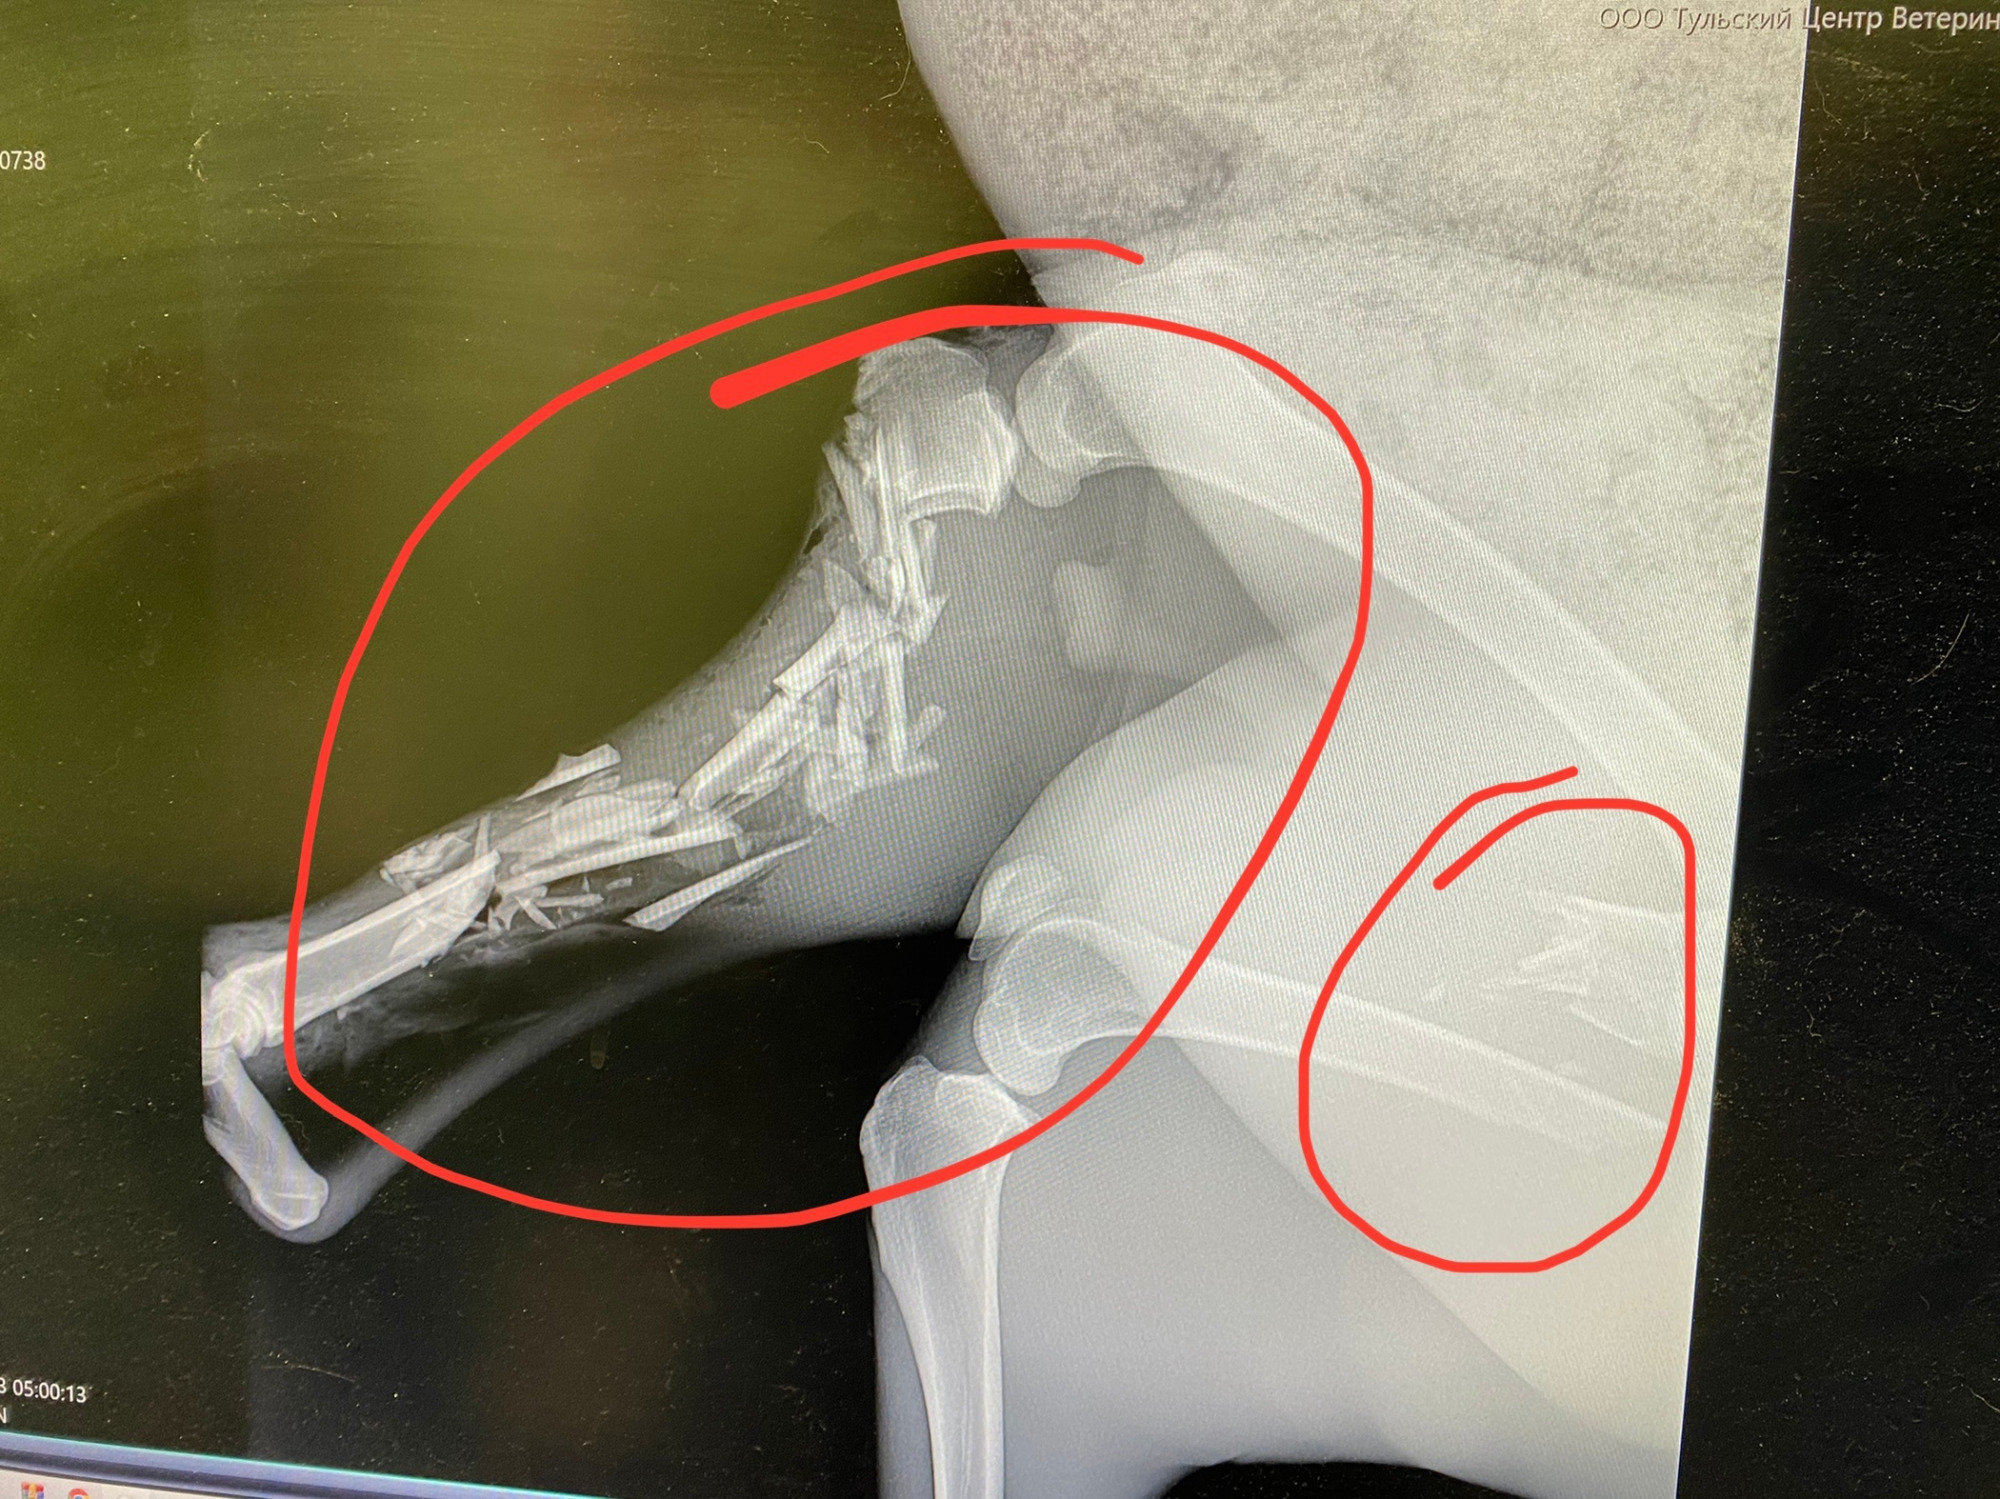

Косулю довезли до ветеринарной клиники в Туле, где животному сделали рентген. Две лапы оказались сломаны.

«Для косули даже небольшой перелом в большинстве случаев заканчивается гибелью из-за стресса и сложностей в восстановительный период. Мы всё-таки сначала предполагали, что можно одну лапу собрать на спицу, а вторую ампутировать, но сегодня проконсультировались с хирургом Станиславом Новицким из «Врачей без границ» и он убедил, что этот случай без шансов и животное придётся эвтаназировать», — отмечает волонтер.